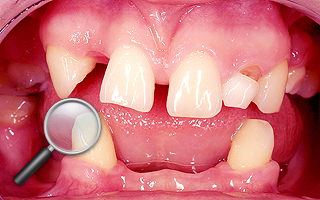

3. Pacjent z szeroką szparą (diastemą) pomiędzy jedynkami.

| 3a. Pacjent przed leczeniem |

3b. Po leczeniu koronami pełnoceramicznymi

pacjent rozważa to samo postępowanie w żuchwie |